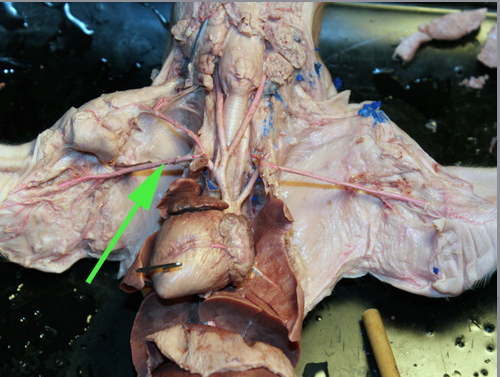

The organ marked by the green arrow is part of the THYMUS gland

The small structure marked by a green arrow is a lymph NODE

The organ marked by the green arrow arrow is the Spleen

The organ indicated by the green arrow is the SPLEEN